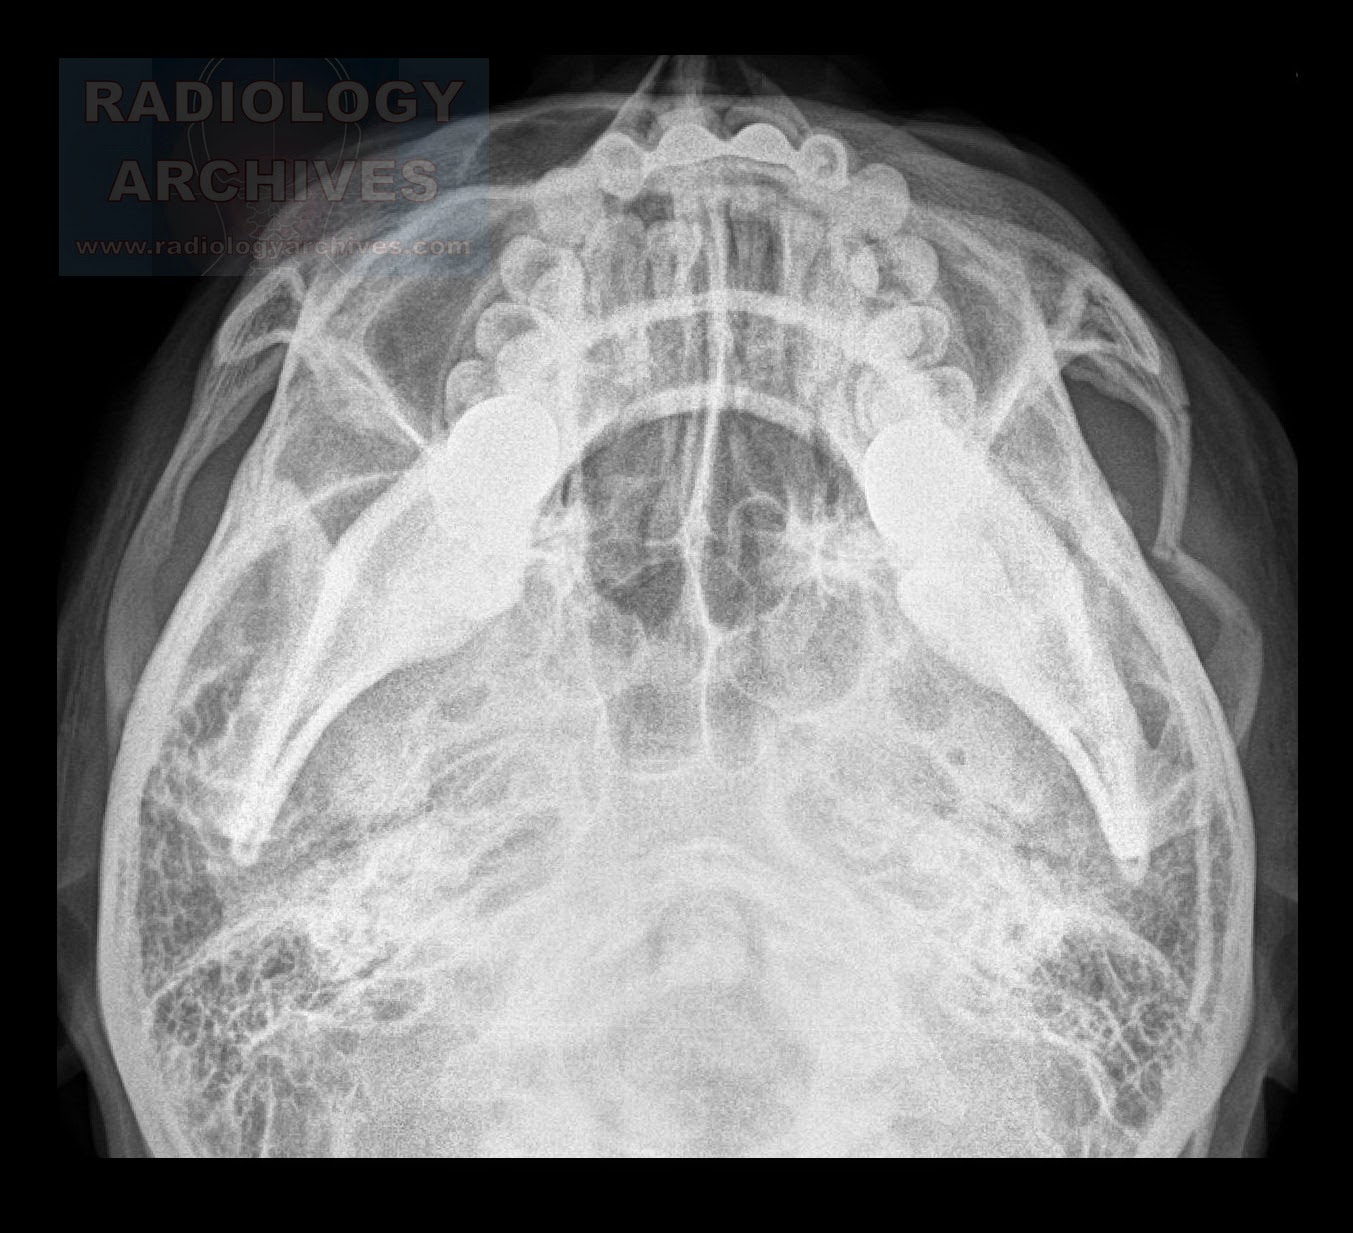

Treatment of isolated zygomatic arch fracture: Inferior orbital rim, and anterior and posterior maxillary sinus fracture of the zygomatic arch and/or diastasis of the temporozygomatic suture.

Of zygomatic fractures in toto, zmc fractures account for 50.7%, zygomaticomaxillary monopod fractures for 25.8%, and isolated fracture of the. This chapter focuses on closed reduction and treatment options for isolated zygomatic arch fractures. Open reduction and according to the site of fracture, various modalities of treatment were used and all the patients achieved satisfactory results without any complications after operation. 100 healthy patients were scheduled for treatment of zygomatic bone fractures. Fractures of the zygomatic arch can occur in isolation. Maxillofacial fractures can have various causes, including traffic accidents, falls, assaults and zygomatic arch fractures. Ct scan showed a fracture of the arch, a depressed fracture. Evaluation of the patients vision is performed as soon as they are awakened from anesthesia and then at regular intervals until they are discharged from the hospital. In these cases, there are usually two fragments, lying freely. Only patients who required open reduction and internal fixation were gillies temporal approach uses a 2.5 cm incision, inclined at an angle of 45° to the zygomatic arch, in the temporal region in the hear bearing area of. Determining whether the zygoma has been patients treated for zygomaticomaxillary complex fractures. Classification and treatment of zygomatic fractures: The fixation points used in the. I have a zygomatic arch fracture what will the doctor do? answered by dr. They comprise fractures of the: Closed reduction for isolated zygomatic arch fractures; The group at highest risk are.